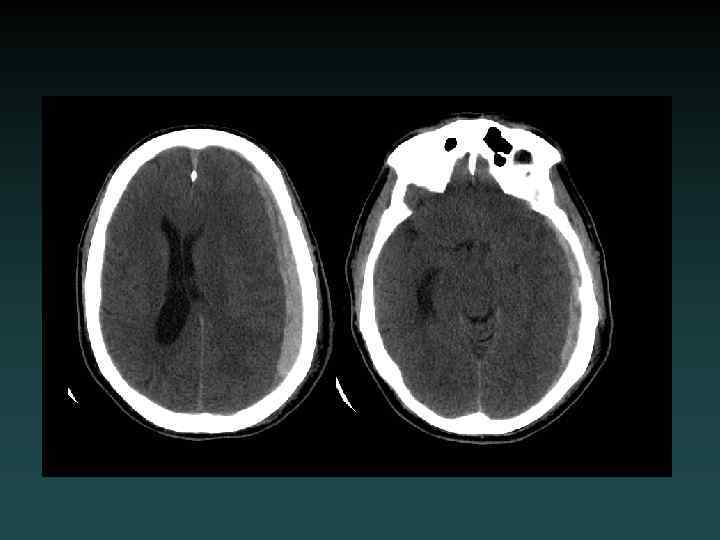

Subarachnoid Hemorrhage • Subarachnoid – Sulci – Cisterns – Ventricles • Trauma – lateral convexities • Aneurysm – basal cisterns • Interpeduncular Cistern – most sensitive

Aneurysmal SAH • Sudden severe headache • HYPERDENSE CSF spaces • Location – Interhemispheric: ACo. A – Sylvian: MCA • HYDROCEPHALUS, VASOSPASM and ISCHEMIA – MUST find the aneurysm! • DSA, CTA and/or MRA